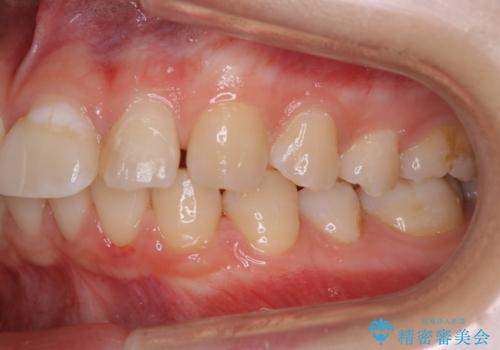

- これからインビザラインでのマウスピース矯正が始まるので、歯石取りをしてほしいとのことでした。

PMTC60分コースを行いました。

歯並が、がたついている場合はなおさら汚れが溜まりやすいです。矯正治療前や矯正中、定期的にPMTCをすることで、矯正治療中の歯肉トラブルを防ぐことにつながります。